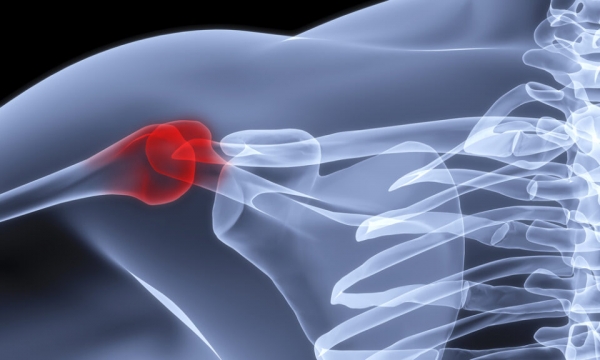

Плечелопаточный периартрит – заболевание, которое сопровождается воспалением в тканях, находящихся вблизи плечевого сустава. Патологический процесс распространяется непосредственно на сам сустав, связки и мышцы. Лечение плечелопаточного периартрита* осуществляется комплексно с использованием медикаментозных и нефармакологических методов.

Заболевание начинается с боли в плече, которая особенно беспокоит при движении рукой. Неприятные симптомы нарастают со временем. Характерно усиление боли в области плечевого сустава и лопатки в ночное время суток. Со временем подвижность руки значительно ограничивается. Больной не может ее поднять, завести за спину.

Если не лечить плечелопаточный периартрит или делать это неправильно, развивается атрофия мышц плечевого пояса. Также возможно появление остеопороза головки плечевой кости. Это способно привести к полной утрате возможности функционирования конечности.